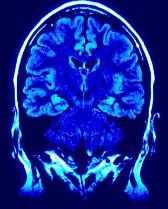

The overwhelming majority of HA are primary HA-most notably tension-type and migraine HA-for which imaging provides no benefit for either diagnosis or treatment. HA can be quite frightening for patients, however, and the concern that a HA indicates some serious, possibly life-threatening disease process is not uncommon. It is therefore not surprising that various imaging tests, now most commonly MRIs and CT scans, are frequently ordered as part of the evaluation process and that patients may believe that they are receiving less than optimal care if such testing is not performed.

The ACR guideline states that contrary to this widely held belief that such testing is needed, it is actually rarely beneficial. A careful history and neurologic exam will determine whether imaging tests are indicated. Research has found that except in patients age 50 years or older, in virtually all cases where HA are symptoms of underlying pathology that needs to be treated, other signs and symptoms besides the pain are also present.2,3 Furthermore, these almost always precede or occur at the same time as the HA. Even for those older than 50, HA indicative of severe pathology are usually accompanied by other problems.

As with testing for LBP, unnecessary testing for HA can actually have a negative effect. Normal variations may be interpreted as potentially serious pathology and can result in further and, at times, more invasive testing. Also, patients who undergo CT scans are exposed to radiation. Finally, there is the financial cost to the patient and the health care system.